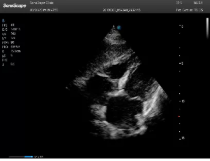

不同的探頭對應于不同的臨床領域,不同的探頭頻率也應用于不同的人體組織。超聲波在人體中的衰減與探頭頻率有關,探頭頻率越高,穿透力越弱,分辨率越高,而探頭頻率越低,穿透力越強,分辨率越低。因此在檢查淺表器官時應選用高頻探頭,而檢查深部臟器時則選用穿透性強的低頻探頭。